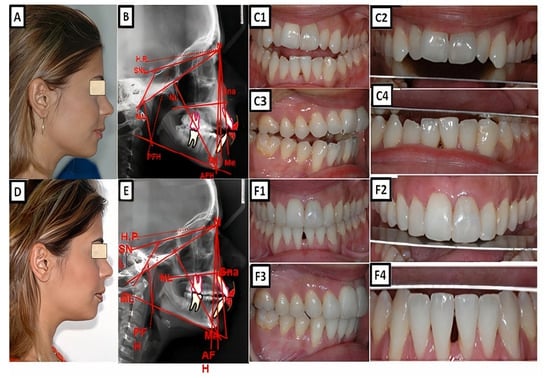

Figure 1.

A biometric photo and images of a patient with Class I. In a Class I molar relationship, the mesiobuccal cusp of the maxillary first permanent molar occludes with the buccal groove of the mandibular first molar (A). In this definition, the malposition of the teeth, except for the first molars, is not included. (B–D) show clinical examples, where (B) shows extraoral, (C) cephalometric, and (D1–D4) intraoral for dental and skeletal Class I without dentoalveolar malposition of the teeth in both jaws.